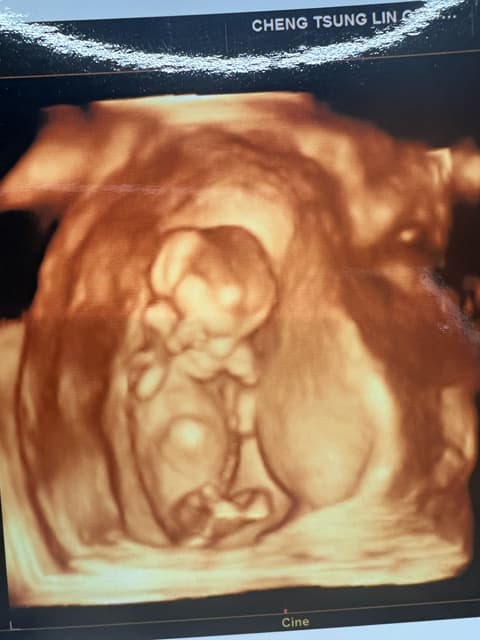

懷孕12週超音波檢查的主要目的是確認胎兒的發育狀況、測量胎兒頭臀徑以判斷孕週數和計算預產期,並檢查胎兒心跳是否正常。此外,醫師會透過超音波觀察子宮內環境,初步篩檢胎兒是否有明顯異常,為後續孕期管理提供重要資訊。

- 測量胎兒頭臀徑(CRL),以判定胎齡和預產期。

- 確認胎兒心跳,評估生命跡象。

- 觀察胎兒數量(單胞胎或多胞胎)。

- 評估子宮內環境,如羊水量、胎盤位置(初步)。